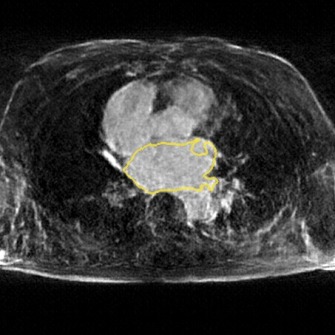

The following images show more samples for 8-fold undersampling. For each of the seven patients of the test set, a random slice showing the left atrium was selected. The contour of the predicted segmentation of left atrium is shown in yellow, the contour of the ground truth segmentation in red.

![[Uncaptioned image]](/html/1806.11216/assets/appendix/c29_post_frame47.jpg)